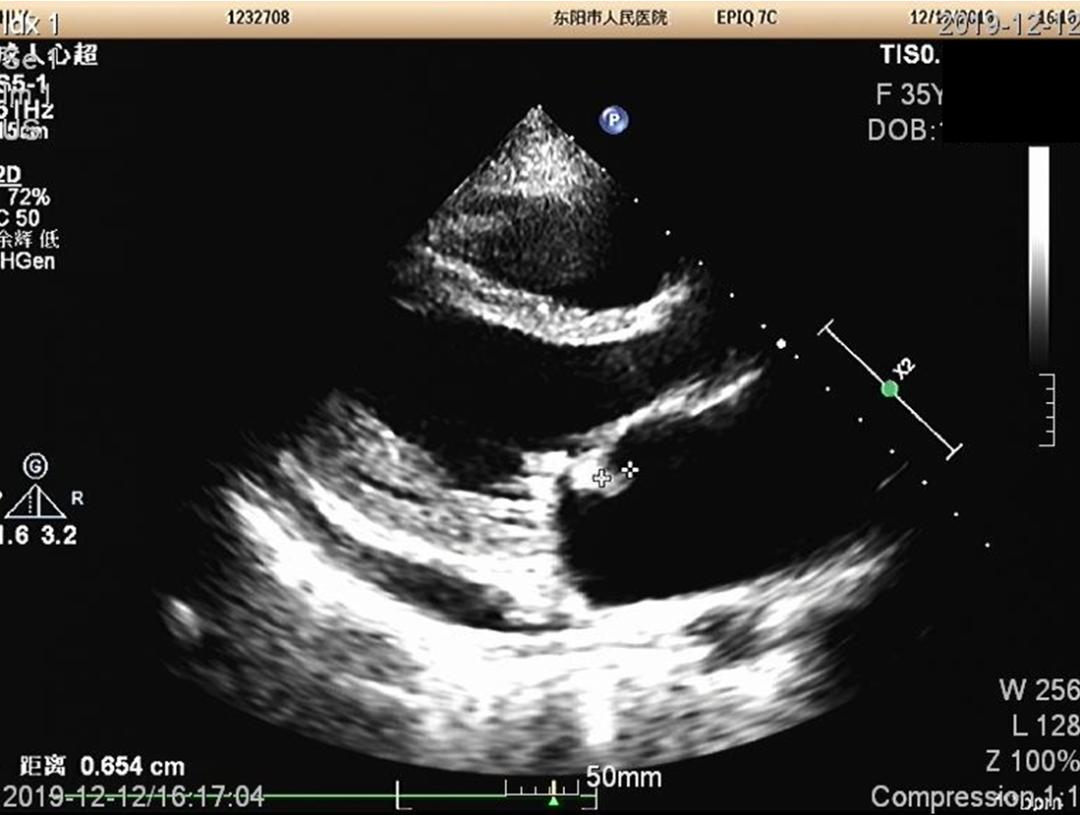

胸骨旁左室长轴切面,显示二尖瓣上有赘生物,这赘生物其他多个切面也可以视察到。

另结合患者血培养阳性,为草绿色链球菌,故诊断明确,为亚急性感染性心内膜炎。

这脾肾肠多脏器加上右髂总动脉,都为心源性栓塞,栓子为二尖瓣赘生物脱落的菌栓。